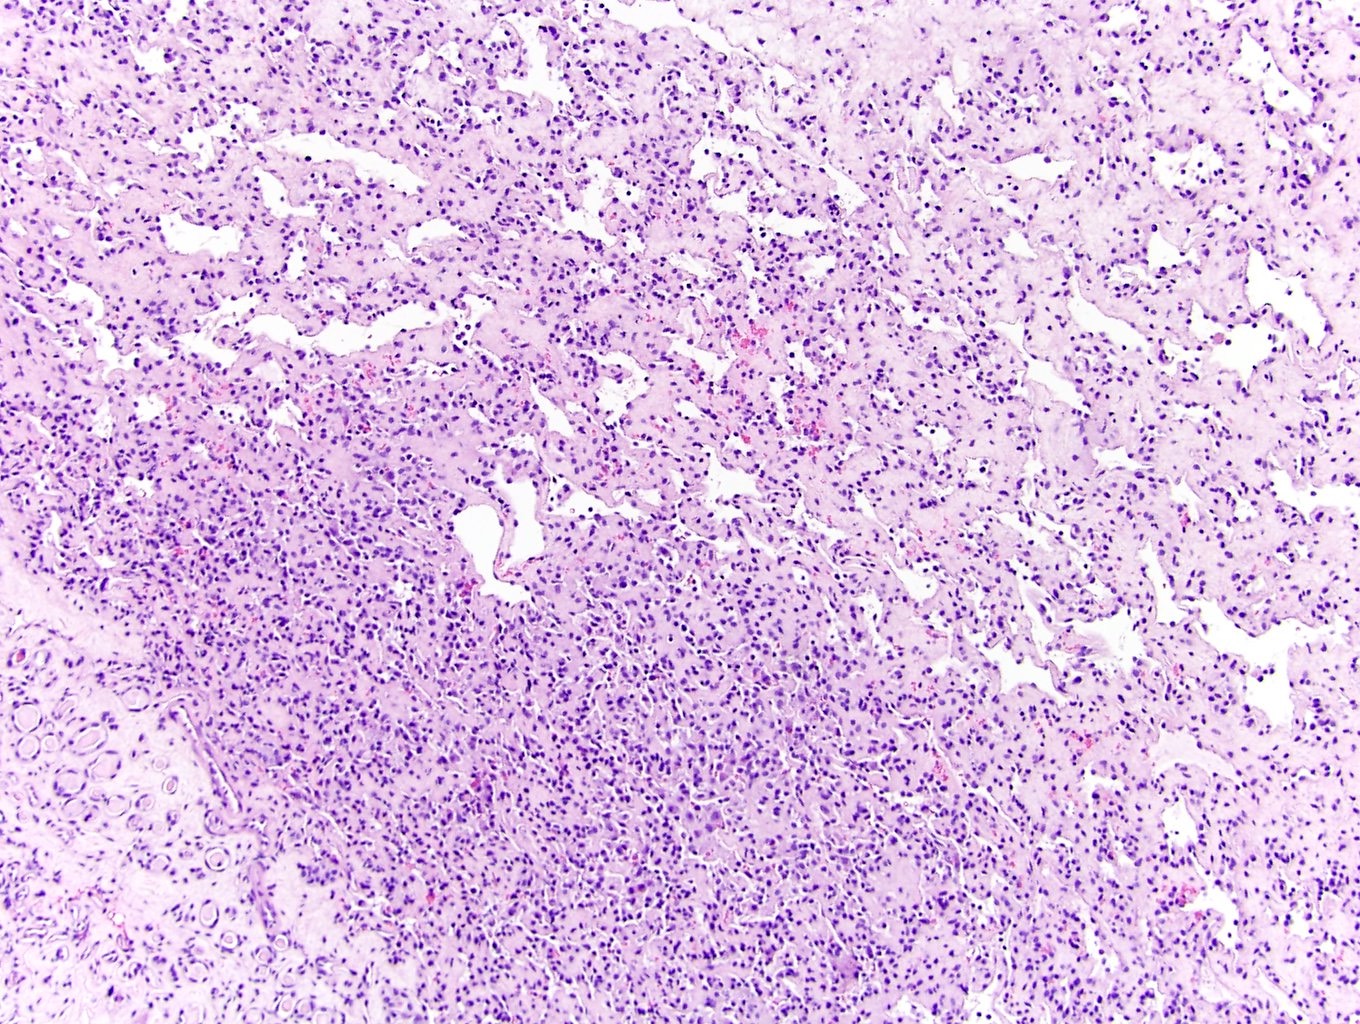

Microscopic (histologic) description

- Circumscribed, unencapsulated proliferation of irregular, blood filled vascular spaces lined by a single layer of endothelial cells

- Anastomosing hemangioma (AH):

- Capillary sized sinusoidal vessels with anastomotic arrangement

- Scattered hobnail endothelial cells

- Extramedullary hematopoiesis, fibrin thrombi, extensive perirenal fat entrapment, intravascular growth and mast cells may be seen (Histopathology 2014;65:309)

- Cytologic atypia and mitotic activity rare

- Regressive changes, including hyalinization, cystic changes and fatty overgrowth (Histopathology 2014;65:309)

Microscopic (histologic) images